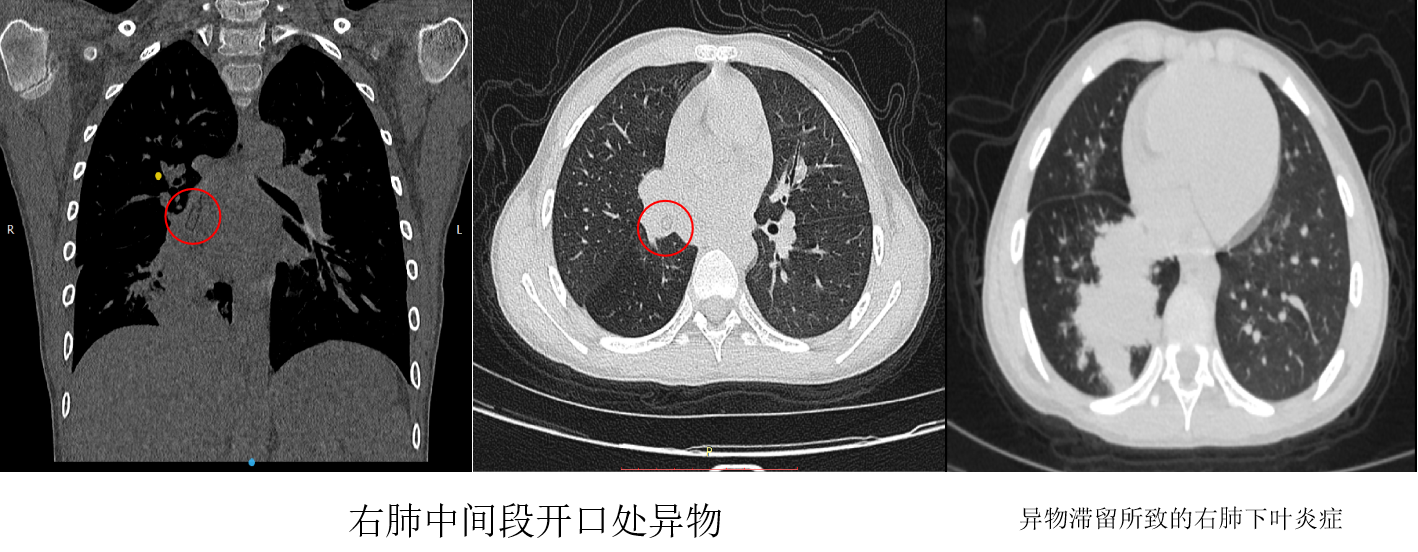

近日,一位9岁男孩捂着胸部走进西安交通大学第二附属医院儿科呼吸专科诊室,父母紧随其后,王慧渊主治医师立即询问此次就诊的原因,男孩母亲述孩子近7个月反复右肺下叶肺炎,经人推荐来到西安交通大学第二附属医院儿童病院呼吸专科门诊就诊,经过详细询问病史发现患儿在7个月前,口含塑料管状异物时突然摔倒,当时并无明显呛咳、呼吸困难等情况,此后孩子出现反复咳嗽伴发热,伴有胸壁疼痛,紧急为患儿完善胸部CT及支气管三维重建,提示右肺下叶支气管内异物,右肺中下叶支气管内粘液栓伴右肺下叶肺不张,右肺多发炎症。

由于异物嵌顿时间长,已有七月之久,住院后患者受到科室的重视,儿科主任杨琳教授看过患儿后指示做好万全准备,制作两套计划,先行支气管镜探查,取异物,若未成功,再联合耳鼻喉科进行硬支气管镜下取异物。王慧渊主治医师、申丹丹住院医师和谢梅副主任护师的默契配合下,凭借着精湛的技术,通过儿童支气管镜精准定位到异物所在位置,并成功将其取出,让孩子转危为安。

异物取出后,患儿安返病房,经过7天充分抗感染治疗,复查胸部CT示右中间段支气管通畅,右肺下叶炎症明显吸收,好转出院。